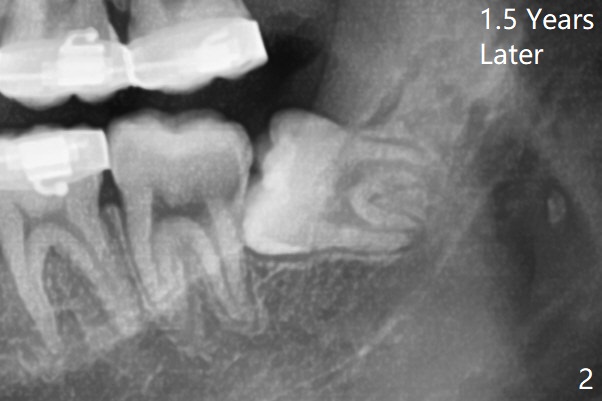

1.5年智齿牙根长长(图二)。1.5月后下颌智齿拔除放置Osteogen Plug(图三)。